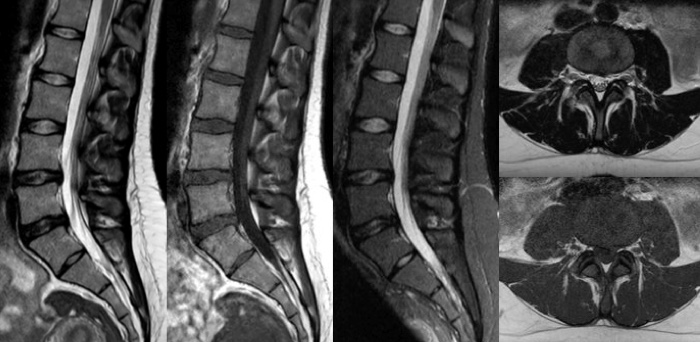

Convierta las imágenes en respuestas hasta un 50% más rápidas

Ponga el tiempo de su lado con Compressed SENSE para reducir el tiempo de exploración hasta en un 50% 2 con una calidad de imagen prácticamente igual. Cree imágenes excepcionales de resonancia magnética con una resolución un 60% más alta para un diagnóstico seguro.

16:30 minutos

Convencional

8:00 minutos

Compressed SENSE

Imágenes de calidad para diagnósticos de calidad

Nuestras bobinas Breeze ultraligeras aportan una versatilidad extraordinaria para obtener imágenes de anatomías complejas y las articulaciones más pequeñas. Además de la excepcional calidad de imagen, ofrece un gran campo de visión de 55 cm y un SNR premium.